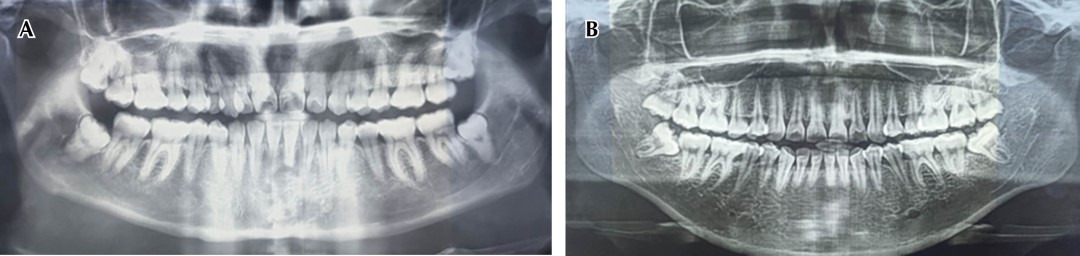

Se recopiló un total de 100 radiografías panorámicas de pacientes de la zona de Acachuén en Michoacán que estaban en un rango de edad de 20 a 65 años de edad; 45 pertenecían a mujeres y 55 a hombres. Para establecer si los pacientes presentaban raíces enanas en los órganos dentales unirradiculares, se empleó la escala de Woelfel, con la que se estableció la discrepancia entre las raíces presentes en la radiografía, las cuales fueron medidas de la porción apical de la raíz al tercio incisal u oclusal de los órganos dentales (Figura 1). Esta medición radiográfica se llevó a cabo en las instalaciones del Centro Mexicano de Estomatología, ubicado en la ciudad de Morelia Michoacán.

Figura 1